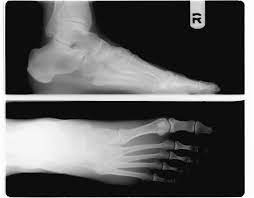

족저근막염 증상

족저근막염은 발바닥을 덮고 있는 근막인 족저근막에 염증이 생겨 발생하는 질환이며, 다음과 같은 증상이 나타날 수 있습니다.

전형적인 증상은 아침에 일어나 처음 발을 디딜 때 느껴지는 심한 통증이 특징적이지만, 모두 같은 증상을 겪는 것은 아니다. 통증은 주로 발꿈치 안쪽에 발생하는 경우가 대부분이고 발뒤꿈치뼈 전내측 종골 결절 부위를 누르면 통증이 발생하기도 한다. 발가락을 발등 쪽으로 구부리면 통증이 심해지기도 한다.

주로 가만히 있을 때는 통증이 없다가 움직이기 시작하면 통증이 발생하고 일정 시간 움직이면 통증이 다시 줄어드는 양상이 많다. 진행된 족저근막염의 경우에는 서 있을 때 뻣뻣한 느낌이 지속되고 하루 일과가 끝나는 시간이 가까울수록 통증의 정도도 심해지는 경우가 있다.